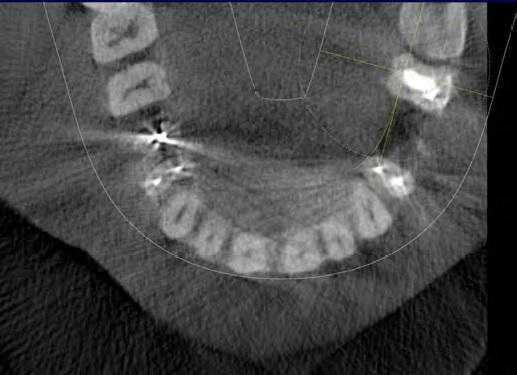

Ученые сообщили, что КЛКТ предоставляет более точные диагностические данные (61%) по сравнения с цифровыми (39%) и обычными (44%) рентгенограммами. Но, несмотря на то, что данные КЛКТ являются более точными, исследователи не призывают к полному вытеснению обычной внутриротовой рентгенографии для выявления периапикальных изменений в обычной клинической практике из-за финансовой и вредностной составляющих. Estrela и коллеги предложили использовать периапикальные индексы, основанные на КЛКТ, для идентификации патологий (Фото 4-6).

Фото 4: Периапикальная киста в переднем сегменте нижней челюсти

А: 3D изображение, показывающее большую кистозную полость

B: Изображение секционного распила, показывающее утрату кортикальной пластинки

C: Аксиальный вид, демонстрирующий утрату кортикальной пластинки с лабиальной стороны и интактную пластинку с лингвальной.

Фото 5: Хронические периапикальные абсцессы около первого правого нижнего моляра

Фото 6: Поражение периодонтальных тканей около левого верхнего второго моляра

Система индексов КЛКТ состоит из 6 ступеней (0-5), исходящих из определения самого большого размера повреждения в каком либо из измерений, и принятие в расчет расширение и разрушение кортикальной кости.

Применяя данный индекс, Low пришел к выводу, что в обнаружение периапикальных патологий лучше использовать КЛКТ недели обычную рентгенографию.

КЛКТ с градиентом теней может оказать помощь в дифференциальном диагнозе кисты и гранулемы. В целом способность выявлять патологии у КЛКТ так же высока, как и у простой КТ. Этот способ может стать важным для пациентов, обращающихся с болевым синдромом или с неточно локализованными жалобами в области ранее леченных или не леченных зубов, на обычном рентгене которых патология не выявляется.